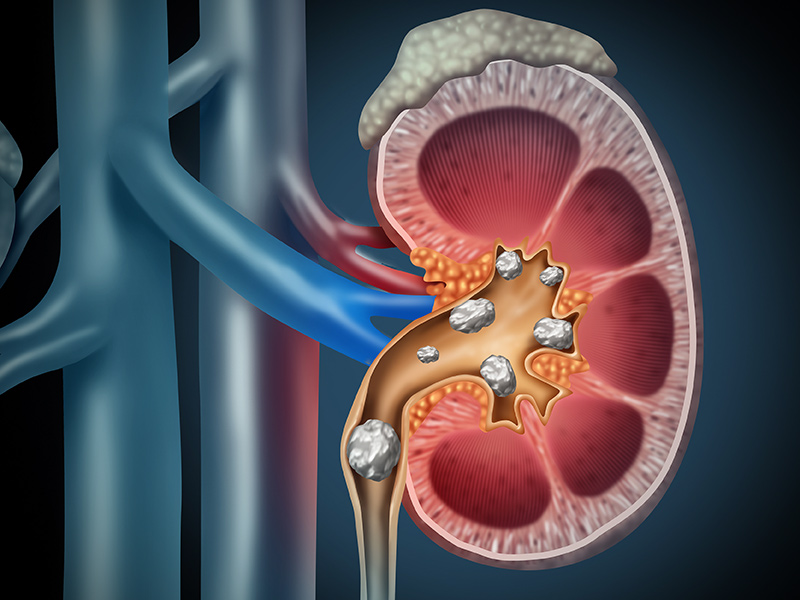

5、泌尿系感染和结石:有些病人长期留置尿管易发生泌尿系感染和结石,应每日擦洗,保持会阴部清洁。鼓励病人多饮水增加尿量,可防止感染及结石,必要时行膀胱冲洗术。